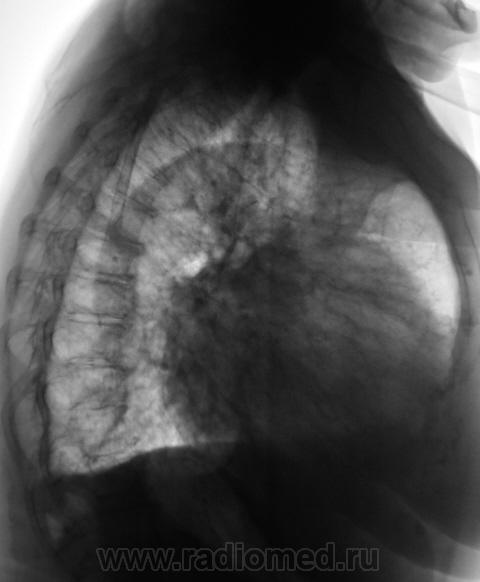

При расшифровке цифровых флюорограмм пациент "взят на контроль". Произведено стандартное исследование.

На рентгенограммах (в отличии от томо) на верхушке ничего не заметил. А так, похоже на митр. недостаточность.